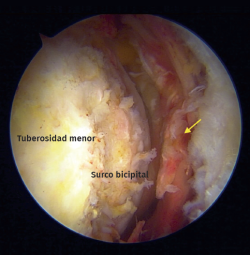

La evaluación radiológica incluyó una resonancia magnética (RM) preoperatoria del hombro afectado y la revisión de forma independiente por parte del cirujano. La RM se utilizó para confirmar el diagnóstico (Figura 1), clasificar la rotura según la escala de Lafosse, evaluar la retracción del tendón, la infiltración grasa (clasificación de Goutallier) en el plano sagital, descartar cambios degenerativos avanzados y evaluar la patología asociada del bíceps (Figura 1).

Figura 1. Imagen axial por resonancia magnética de una rotura subescapular aguda de espesor completo. Flecha: rotura del tendón subescapular.